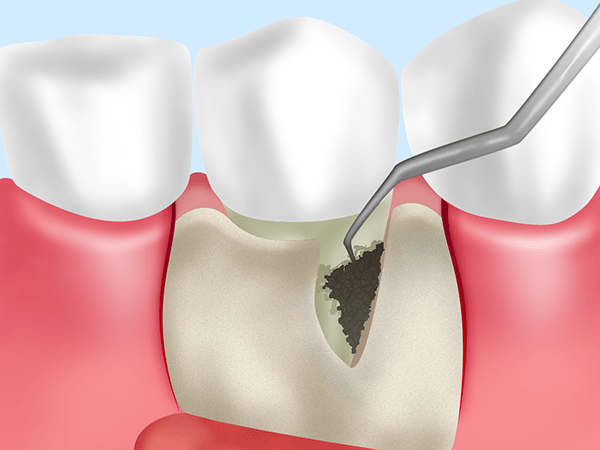

スケーリング

毎日の歯みがきでは落としきれないプラークや歯石を除去します。

ルートプレーニング

スケーリングでは落としきれない歯周ポケットの奥のプラークや歯石を除去してから歯根を滑らかに仕上げます。

歯周ポケットそうは術

局所麻酔を行ったうえで、歯周ポケットの奥深くに入り込んだプラークや歯石、感染歯肉の組織を除去します。

フラップ手術

局所麻酔を行ったあと、歯肉を切開して歯根を露出させ、プラークや歯石を除去します。そして歯肉を縫合します。